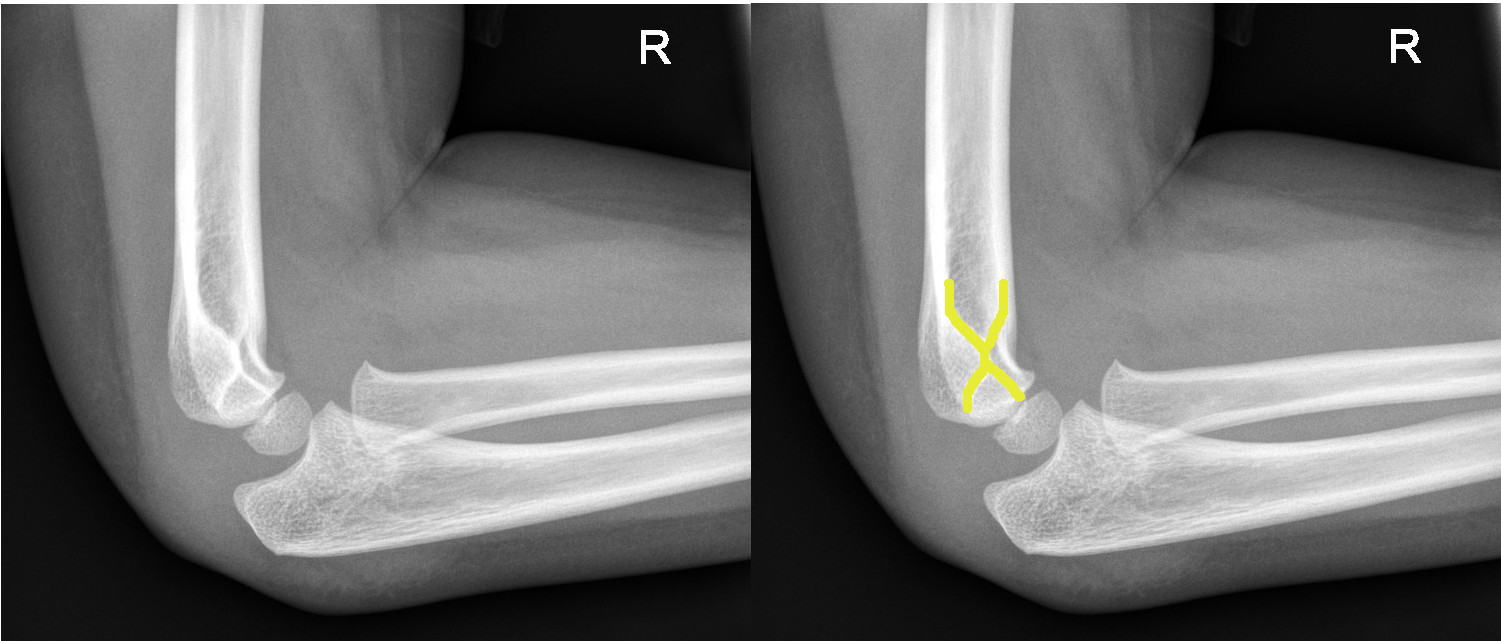

|

Supracondylar fracture evident on the AP view |